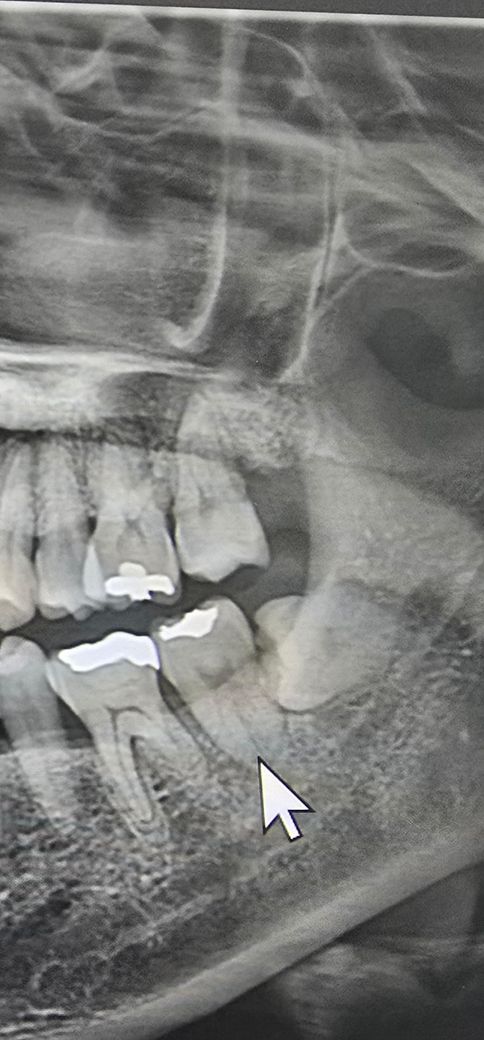

사진상으로 보았을 때 뒤쪽 사랑니를 뽑고 나면 앞에 있는 어금니쪽 뒷 뿌리가 그대로 바깥으로 노출될 것으로 보입니다. 이러한 경우에는 신경치료 이후 씌우는 치료까지 고려해야 하나 현재 3도 이상의 동요도가 있다면 치아를 뽑아야 할 수도 있습니다. 또한 통증이나 불편감이 너무 심하므로 약을 드셔도 증상이 호전되지 않는다면 빨리 다시 치과를 가는 것이 맞습니다.